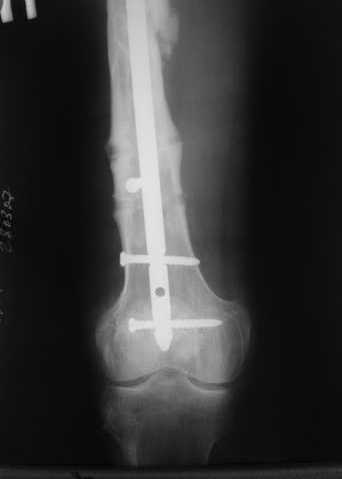

Как обещал, выкладываю рентгенограммы нашего пациента.

Пациенту М., 30-ти лет, 1,5 года назад в одной из московских больниц был выполнен остеосинтез бедренной кости штифтом UFN (диаметр штифта 9 мм).

К нам больной поступил с признаками ложного сустава бедренной кости, перелома

штифта и дистального блокирующего винта (images 1,2,3).

27 марта выполнено удаление блокирующих винтов (сломанный винт пришлось высверливать цапфен-бором), сломанного штифта (дистальный фрагмент удален через канал, образованный разверткой из коленного сустава - image 4),

рассверливание костно-мозгового канала, реостеосинтез штифтом UFN (при проведении штифта в дистальном отломке мы использовали поляризующий винт, диаметр штифта 10 мм). После операции в связи гемартрозом дважды (на 1 и 3 сутки) выполняли пункцию коленного сустава. Сейчас признаков скопления жидкости в полости сустава нет. Послеоперационные рентгенограммы - images 5, 6, 7.